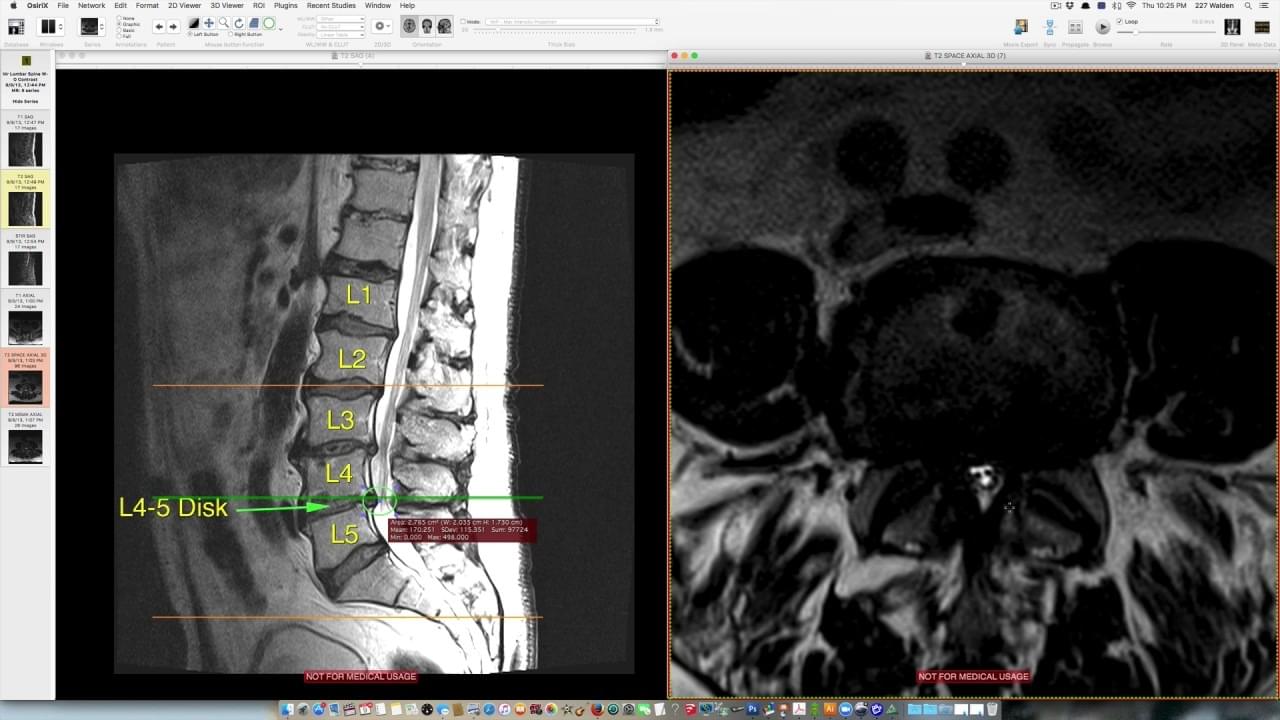

“Just a few months ago, you had three degenerative discs, constant pain, and one of the worst spinal scans I’ve ever seen…”

He looked up at me. “But now? These scans look normal. Your spine is aligned, the discs look healthy, and you’re moving without pain. Did you get surgery?”